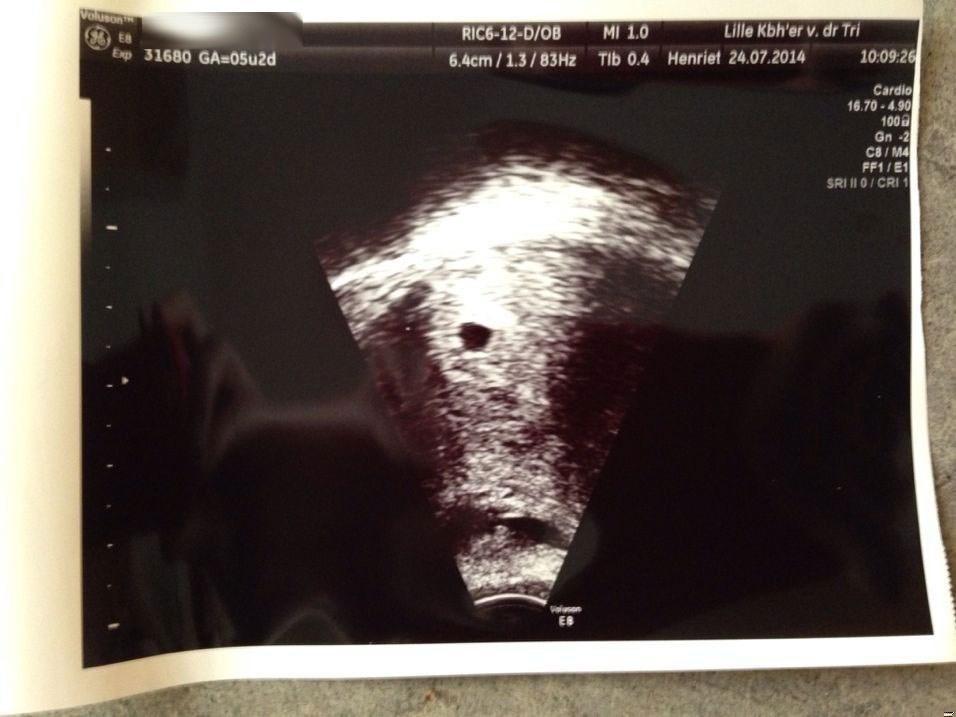

Hej Julie

Jeg fik foretaget en scanning hos LilleKBH'er i går for 300 kr.

Bare for at se at alt så ud som det skal.

Jeg er kun 5+4 men har haft symptomer i 3 uger, men vi er meget forskellige, og jeg har altid været meget sensitiv.

Det er muligt at se hjertet slå i uge 6, så det er planen at jeg skal derhen igen d. 1.8.

Du burde kunne se det uden problemer.

Min lille blop ser sådan her ud lige nu.

Held og lykke!

Vedhæftede fotos (klik for at se i fuld størrelse)